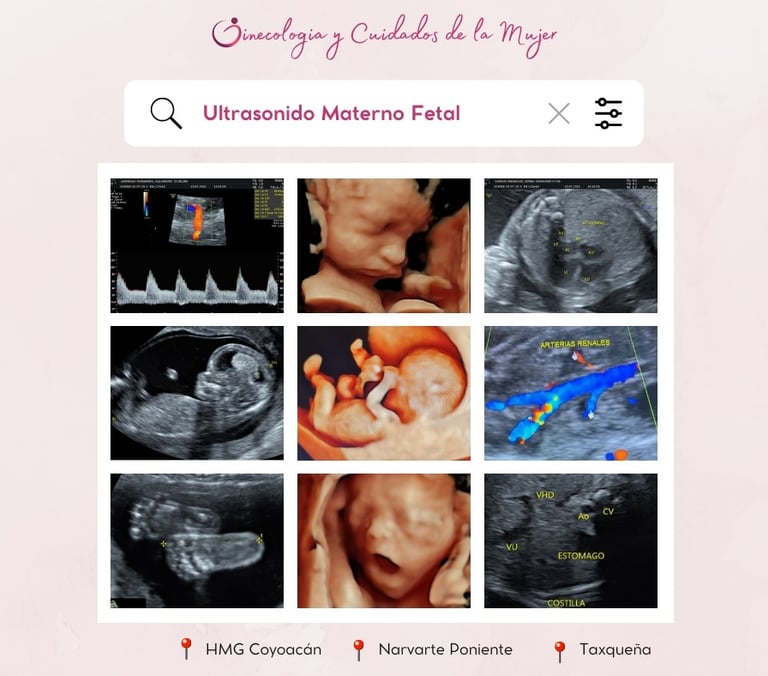

Contamos con médicos especialistas en Medicina Materno Fetal, certificados por la Fetal Medicine Foundation para realizar; Ultrasonido estructural (semana 11-14), ultrasonido estructural semana (18-24), Ultrasonido de crecimiento (semana 28-34), ultrasonido 4D, Ultrasonido con Doppler fetal.